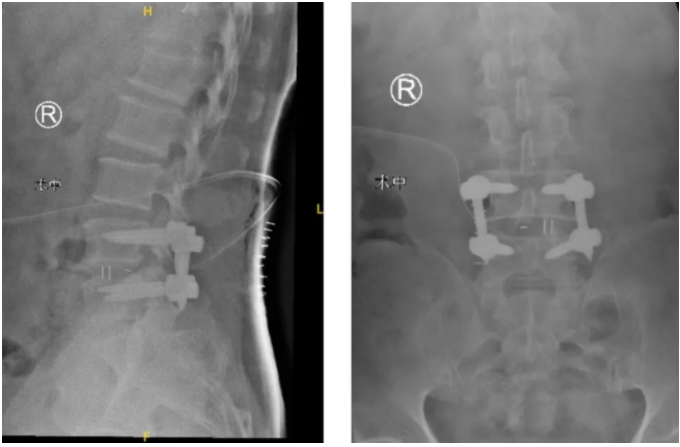

在智能骨科机器人+3D裸眼显微镜的辅助下,王先生的手术很成功,术后皮肤表面只留下了3cm的小切口!

术后

目前,王先生已经可以下地进行康复锻炼,不论步态还是精气神,与刚入院时都形成了鲜明对比。